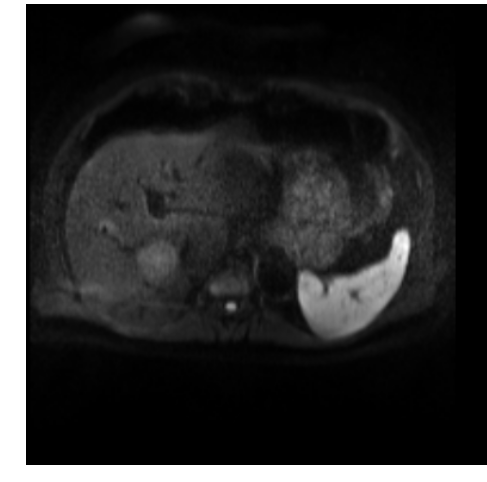

In clinical routine, manual or semi-manual segmentation techniques are applied to interprete CT and MRI images that have been acquired in the diagnosis of the liver. These techniques, however, are subjective, operator-dependent and very time-consuming. In order to improve the productivity of radiologists, computer-aided methods have been developed in the past. However, an automated robust segmentation of combined liver and lesion remains still an open problem because of challenges as a low-contrast between liver and lesion, different types of contrast levels (hyper-/hypo-intense tumors), abnormalities in tissues (such as after surgical resection of metastasis), size and varying number of lesions. As shown in figure 1 the heterogeneity in liver and lesion contrast is very large among subjects. Different acquisition protocols, differing contrast-agents, varying levels of contrast enhancements and dissimilar scanner resolutions lead to unpredictable intensity differences between liver and lesion tissue. This complexity of contrast differences make it difficult for intensity-based methods to generalize to unseen test cases from different clinical sites. In addition, the varying shape of lesions due to irregular tumor growth and response to treatment (i.e surgical resection) reduce efficiency of computational methods that make use of prior knowledge on lesion shape.

Figure 1: Liver and liver lesions slices in CT and diffusion weighted DW-MRI as well as the corresponding histogram for liver and lesions pixels in the respective modality. The shape, size and level of contrast vary for different lesions. As the histograms indicate, there is a significant overlap between liver and lesion intensities, leading to a low overall contrast.